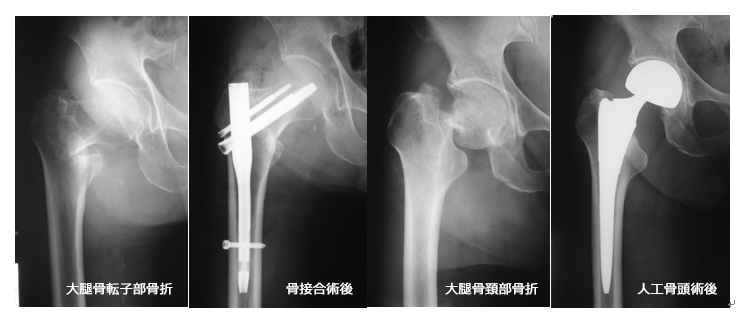

2. 股関節の外傷

また高齢者では骨粗鬆症を基盤とした大腿骨近位部の骨折や、骨盤(恥骨、坐骨など)の骨折などがあります。レントゲンで診断困難な場合なこともありますが、MRIを行うことで早期の診断が可能となります。

高齢者の大腿骨近位部骨折の場合は、骨折後長期の臥床・安静により、歩行能力が低下することが多いため、ほとんどの患者様が手術適応となり、できるだけ早期に手術を行いリハビリを行うことで、受傷前の活動性を維持することができます。また大腿骨近位部骨折の患者様はほとんどが骨粗鬆症を合併しており、反対側の股関節の骨折発症予防のためにも骨粗鬆症治療の介入の必要があります。